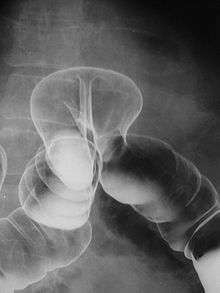

A lower gastrointestinal series is a medical procedure used to examine and diagnose problems with the human colon (large intestine). Radiographs (X-ray pictures) are taken while barium sulfate, a radiocontrast agent, fills the colon via an enema through the rectum.

This test may be done in a hospital or clinic. The patient lies on the X-ray table and a preliminary X-ray is taken. The patient is then asked to lie on the side while a well lubricated enema tube is inserted into the rectum. As the enema enters the body, the patient might have the sensation that they have to have a bowel movement. The barium sulfate, a radiodense (shows as white on X-ray) contrast medium, is then allowed to flow into the colon. A large balloon at the tip of the enema tube may be inflated to help keep the barium sulfate inside. The flow of the barium sulfate is monitored by the health care provider on an X-ray fluoroscope screen (like a TV monitor). Air may be puffed into the colon to distend it and provide better images (often called a "double-contrast" exam). If air is used, the enema tube will be reinserted if it had been removed and a small amount of air will be introduced into the colon, and more X-ray pictures are taken.

In a healthy colon, barium should fill the colon uniformly and show normal bowel contour, patency (should be freely open), and position.